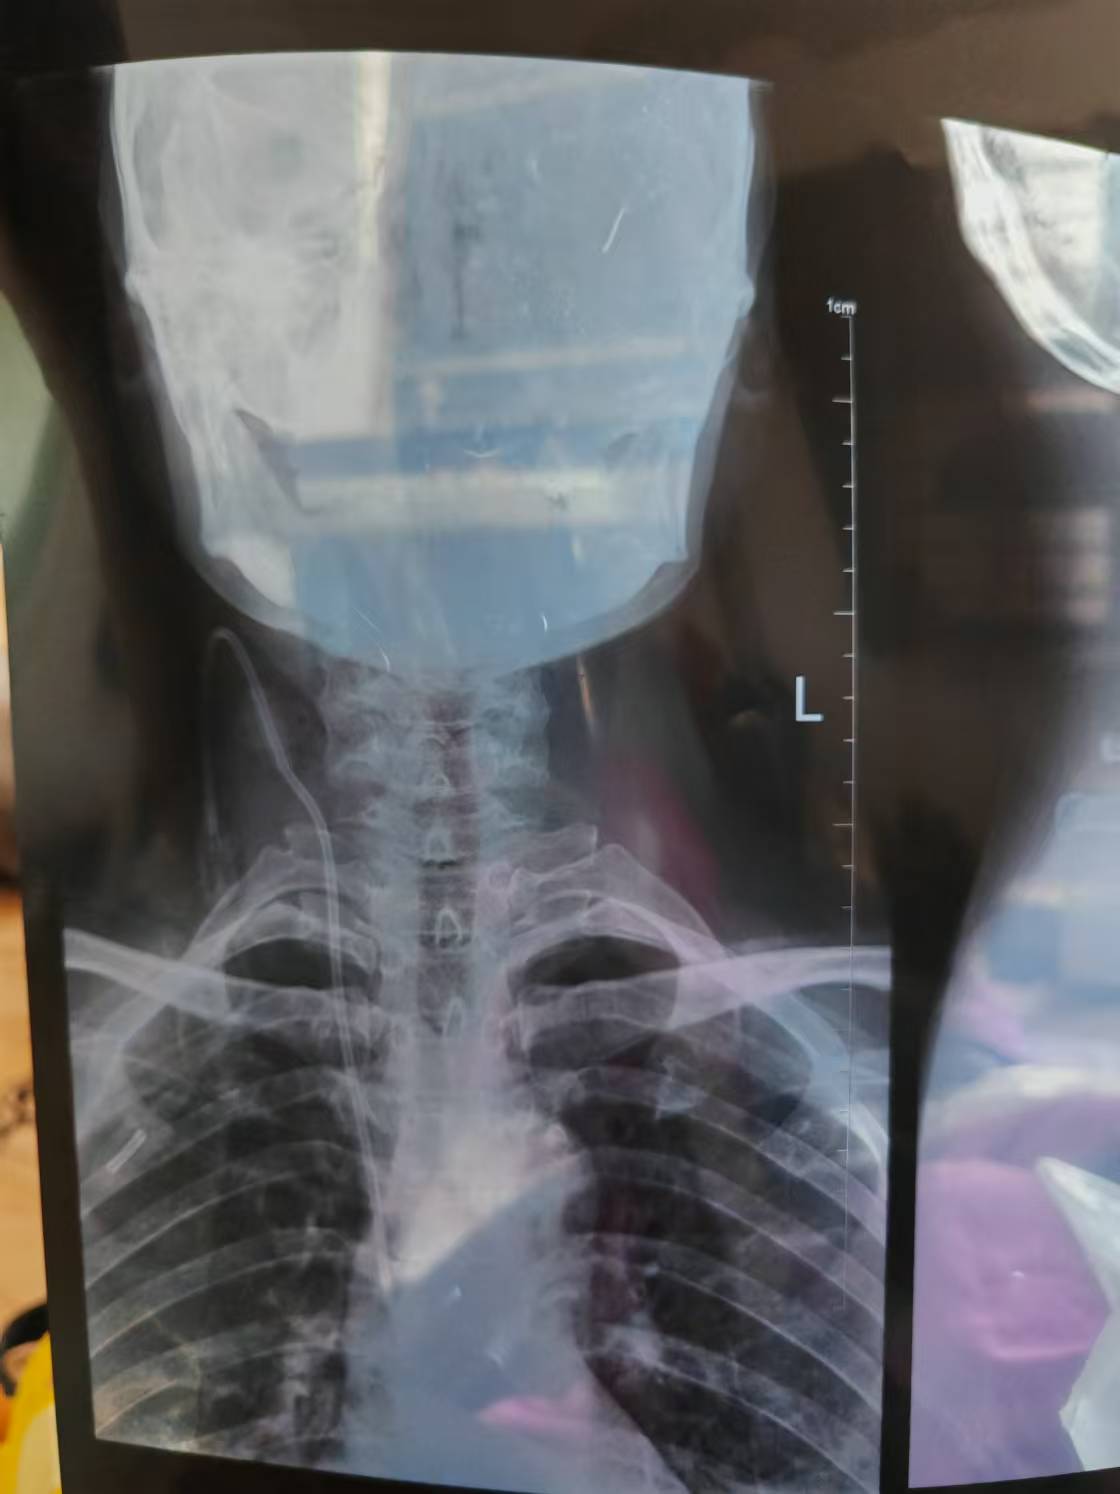

• 诊断:寰枢椎脱位

• 日期:2023.10

• 医院:北京301医院

• 主刀:彭宝淦

• 术后状况:手术方式是用肽缆把寰枢椎缠上,手术手脚麻木,医生让观察一段时间,一个月后手脚无力,背部僵硬。

• 术后影像: